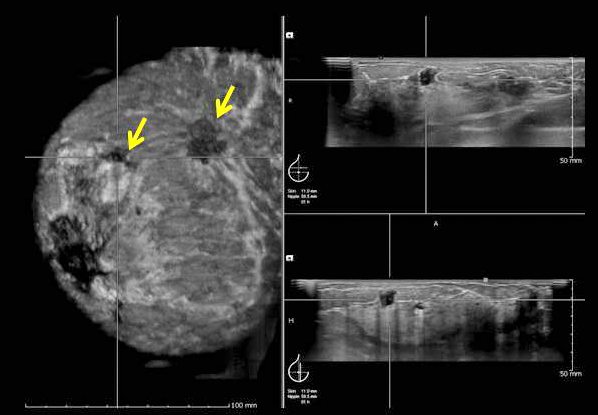

• Το υπερηχογράφημα μαστών χρησιμοποιείται επίσης στην σταδιοποίηση των ασθενών με καρκίνο του μαστού, επιτρέποντάς μας να μετρήσομε με ακρίβεια το μέγεθος του όγκου και να εντοπίζομε επιπρόσθετες εστίες σε περιπτώσεις πολυεστιακής εντόπισης της βλάβης.

Διαδοχικές μετρήσεις του όγκου πρίν και μετά από τη χημειοθεραπεία μπορούν να χρησιμοποιηθούν για να εκτιμήσομε αντικειμενικά την απάντηση του ασθενή στο σχήμα της χημειοθεραπείας.

Η μαστογραφική ανίχνευση τού καρκίνου είναι αντιστρόφως ανάλογη της πυκνότητας του μαστού αλλά βελτιώνεται σημαντικά με τη συμβολή της υπερηχογραφίας ακόμη και σε μικρού μεγέθους μάζες.